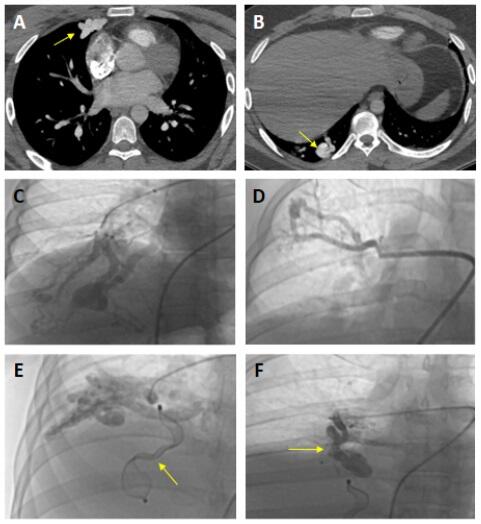

A 27-year-old man presented to the emergency department with complaints of syncope, dyspnea, and fatigue. Physical examination revealed left-sided mild hemiparesis, platypnea, and continuous murmur on right middle lobe lung auscultation. Pulse oximetry analysis revealed worsening hypoxemia during the upright position (78%) and ameliorating hypoxemia during the supine position (84%). Thoracic computed tomographic angiography (CTA) demonstrated multiple pulmonary arteriovenous malformations (PAVM) (Figure A,B). We suspected hereditary hemorrhagic telangiectasia. However, the patient did not meet the other diagnostic criteria except for PAVMs. Pulmonary angiography was performed to demonstrate the PAVMs in detail, and it was determined that the right-sided malformations were enormous, while the left-sided malformations were relatively small (Figure C, D, E, F, Video ).